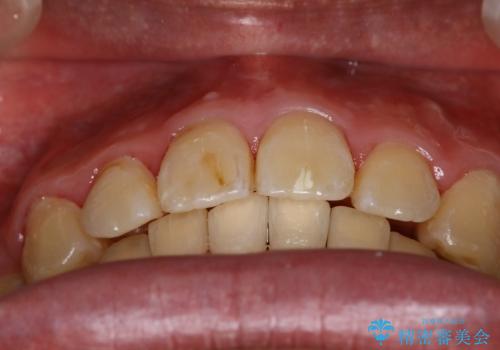

- 上顎前歯の突出感と下顎前歯のガタつきが主訴で来院されました。

出っ歯とガタつきの改善を行うには抜歯が必要と診断し、上下左右第一小臼歯を抜歯する計画を立てました。

抜歯する事で歯の移動量が大きいことからワイヤー表側矯正装置で治療を行うことになりました。